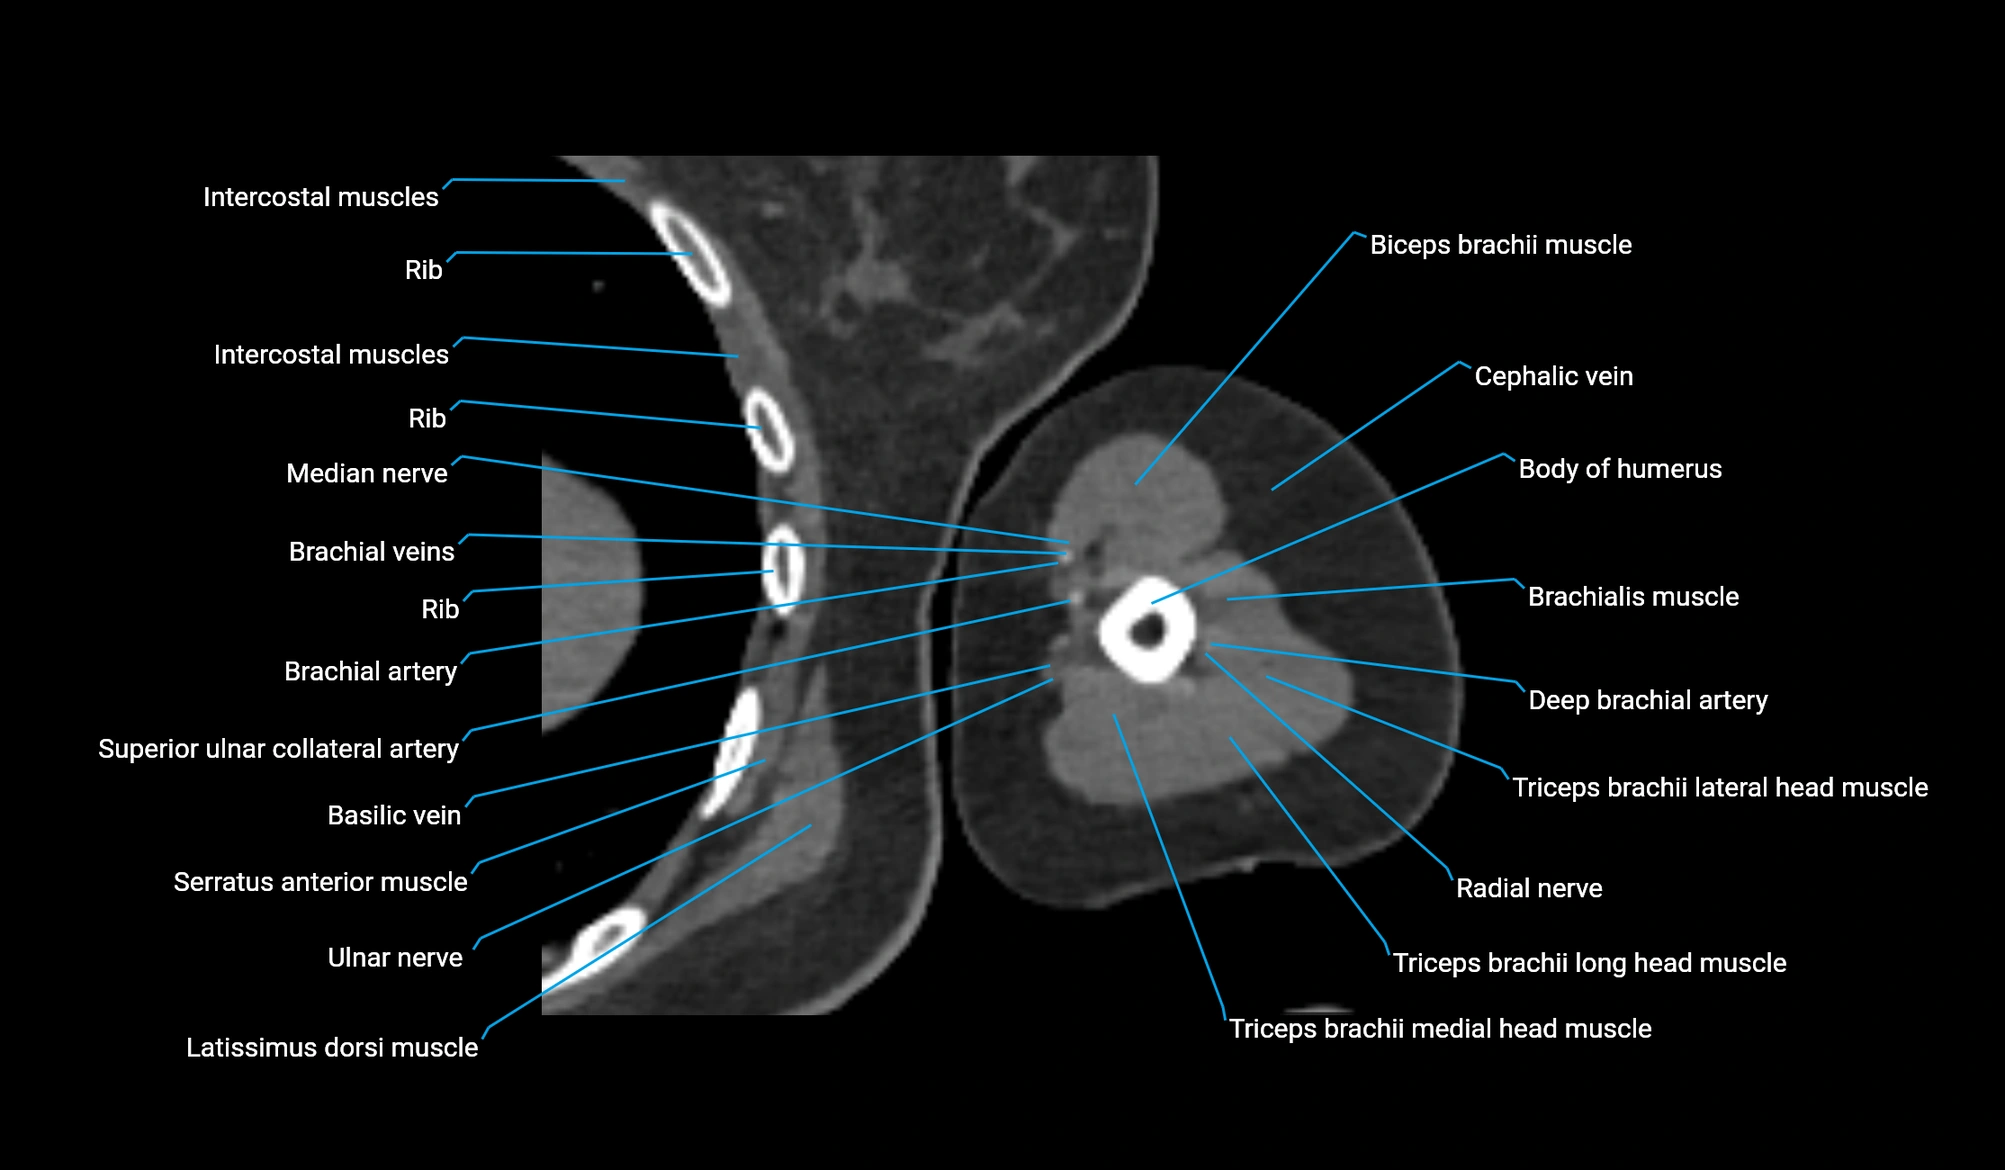

CT image